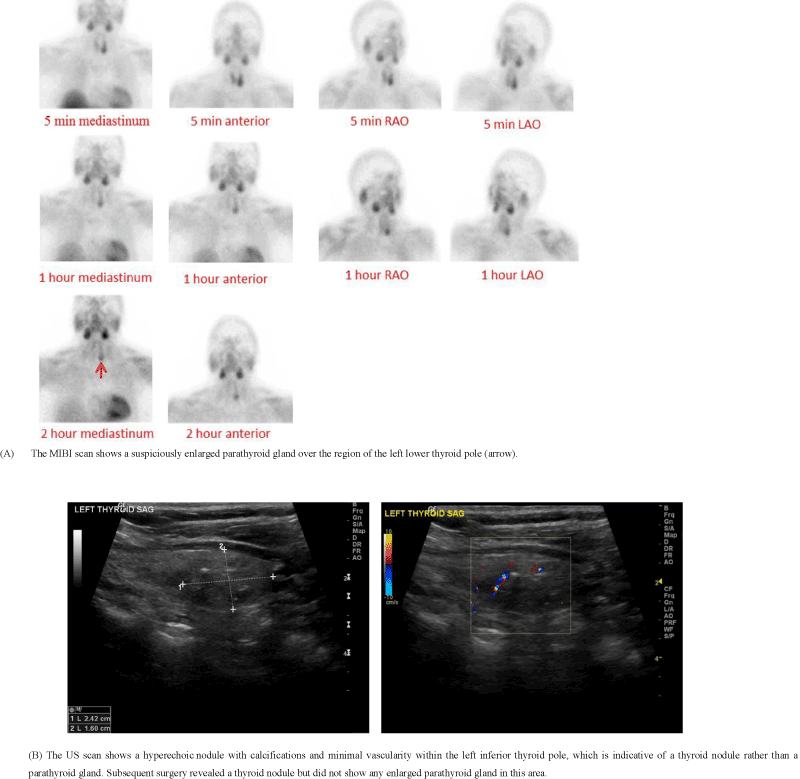

Figure 1. A 71-year-old female presented with a PTH level of 69.5 pg/ml and a calcium level of 8.8 mg/dl, which is clinically suspicious for PHPT.

The limitations of MIBI include: 1) false-positive findings due to thyroid nodules (Figure 1); 2) false-negative or low confidence results due to the relatively small size of enlarged parathyroid gland(s) (Figure 3); 3) suboptimal results due to body habitus, motion, patient intolerance to lengthy procedures, or an adverse tracer reaction (Figure 2B); 4) information arising from a predominant, hyperfunctioning parathyroid gland that overwhelms the uptake activity from the other non-dominant, enlarged parathyroid glands (Figure 4); 5) the inability to portray an accurate relationship between an enlarged parathyroid gland and its surrounding structures (Figure 5); and 6) the inability to detail concurrent thyroid nodules (Figure 6).